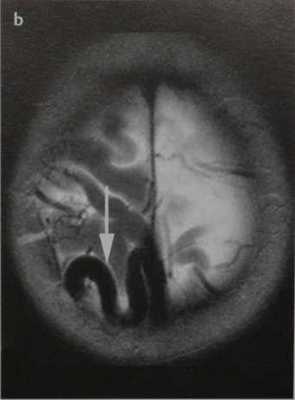

Пиальная артериовенозная мальформация головного мозга . МРТ, Т2-ВИ в аксиальной плоскости (а, b). ДСА в боковой проекции после введения КС в правую внутреннюю сонную артерию (с). Тубулярное отсутствие сигнала от потока в очаге АВМ (черные стрелки) на Т2-ВИ (а). Гипоинтенсивная гематома на Т2-ВИ (дезоксигемоглобин; а, белые стрелки).

Тубулярное отсутствие сигнала на поверхности головного мозга (вена; b, стрелка).

Определяется раннее контрастное усиление поверхностной мозговой вены, начинающейся от ветвей средней мозговой артерии (с, стрелка), и виден располагающийся между ними клубок сосудов (очаг, с)